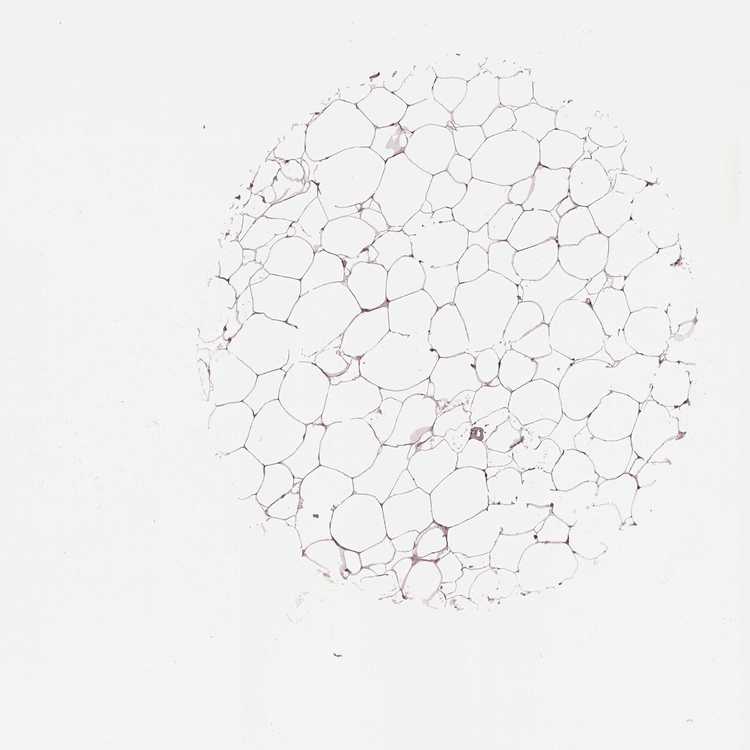

BREAST - Antibody stainingi

Antibody staining in the annotated cell types in the current human tissue is reported as not detected, low, medium, or high, based on conventional immunohistochemistry profiling in selected tissues. This score is based on the combination of the staining intensity and fraction of stained cells.

Each image is clickable and will lead to virtual microscopy that enables deeper exploration of all samples and also displays staining intensity scores, fraction scores and subcellular localization as well as patient and tissue information for each sample.

Antibody HPA023197

Adipocytes Medium

Glandular cells Medium

Myoepithelial cells Medium